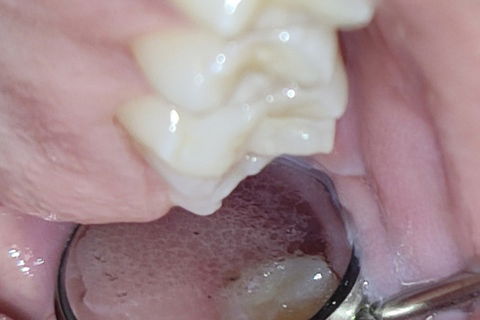

Leito cirúrgico após as exodontias

Suturas 37 /38 imediatas